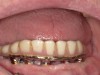

Fig 9. An implant retained over-denture was upgraded to a fixed zirconia hybrid.

Figure 9